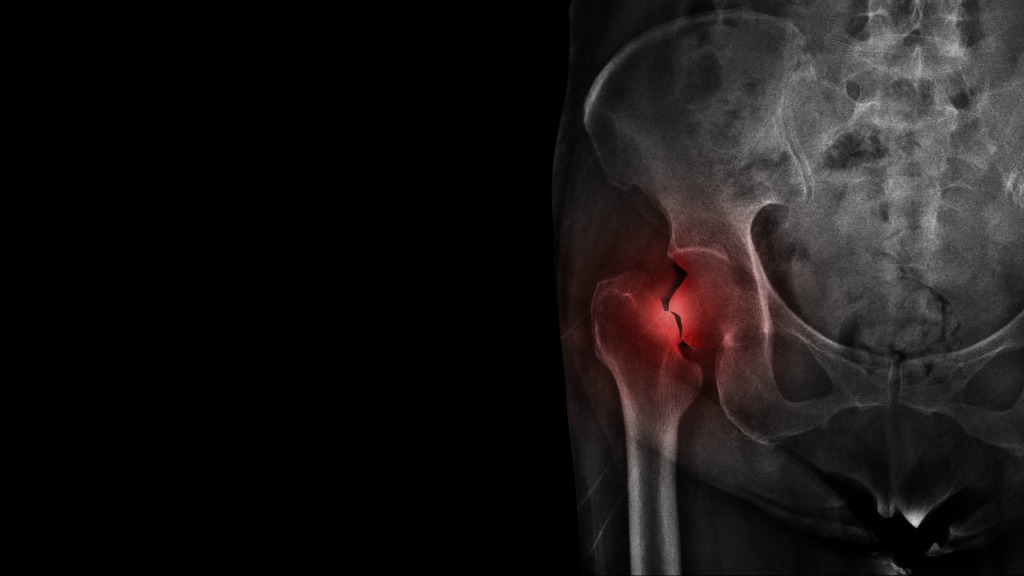

骨粗しょう症とは、骨密度が低下することで骨が脆くなり、

骨折しやすくなってしまう病気のこと。

酷いときはくしゃみや少し手をついたなどの軽い衝撃で骨折してしまうことも

あります。

自覚症状が現れにくく静かに進行していくことも多く、気づいたら骨折していた、骨折により介護が必要になった、など生活の質に大きく関わるため、予防や早めの治療が必要です。

CBDは骨折の治療にも効果的

さらに、2015年の研究ではCBDが骨折の治療にも役立つ可能性があることを

発見しました。

実験では、大腿骨が骨折したラットにCBDのみ、もしくはCBDと同じく

「カンナビノイド」のひとつであるTHC(テトラヒドロカンナビノール)のいずれかを投与し、その影響を観察しました。

結果、THCでは大きな効果が得られませんでしたが、CBDのみで治療した

ラットの治癒が早く、さらに同じ部位で骨折する可能性も低くなったことが

報告されました。

まだ研究の段階ではありますが、今後さらに研究が進めば、骨粗しょう症

だけでなく、スポーツや日常生活での骨折の治療や予防にCBDが役立つ日が

来るかもしれません。